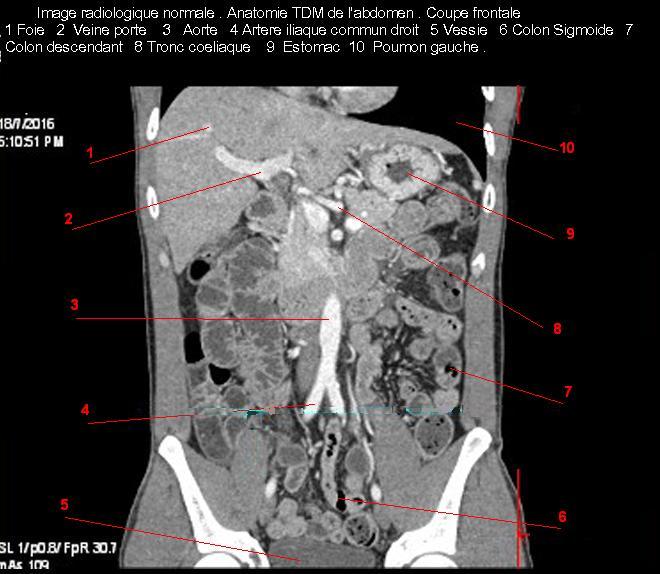

Image TDM

normale du foie :

Image TDM du foie

en coupe coronale ( axiale ) a travers tronc

portale bifurcation portale et vesicule biliaire . Double de click pour agrandir . |